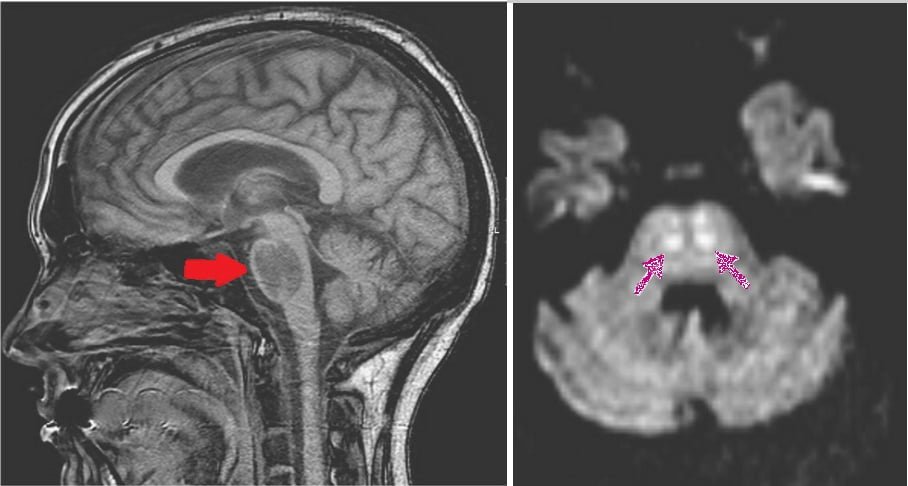

Yani doktorlar, Lee’nin ölmeden önce esrar ve su içtiğini göz önüne aldığında tükettiği suyun böbrekleri için fazla gelmiş olabileceğini buldu. Bu durumun ise beyinde ödeme neden olduğu aktarıldı. Zira beyin ödemi, kandaki sodyum yoğunluğundaki azalmayla ilişkilendirildi. Lee’nin beyni öldüğünde bin 575 gram gelmişti. Normalde bin 400 gram olması gerekiyordu.